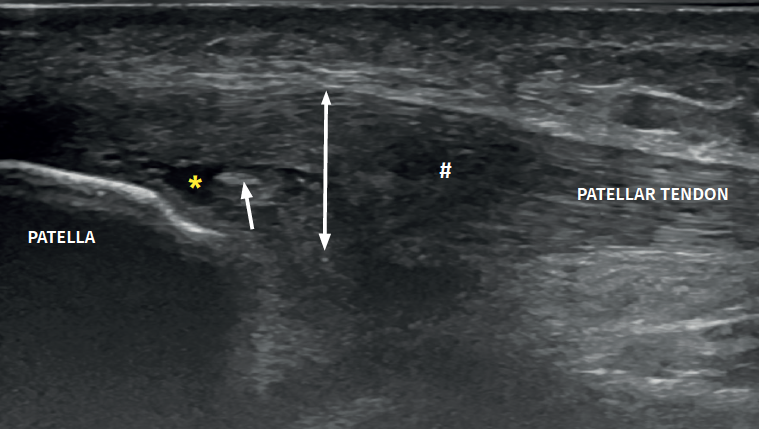

Tendinopatía rotuliana con rotura intrasustancia

En esta imagen longitudinal puedes ver un tendón rotuliano con varias alteraciones simultáneas: la doble flecha muestra el engrosamiento del tendón, la almohadilla (#) marca la zona donde el patrón fibrilar está alterado y la ecogenicidad reducida, el asterisco señala una rotura intrasustancial y la flecha indica una zona de fibrosis.